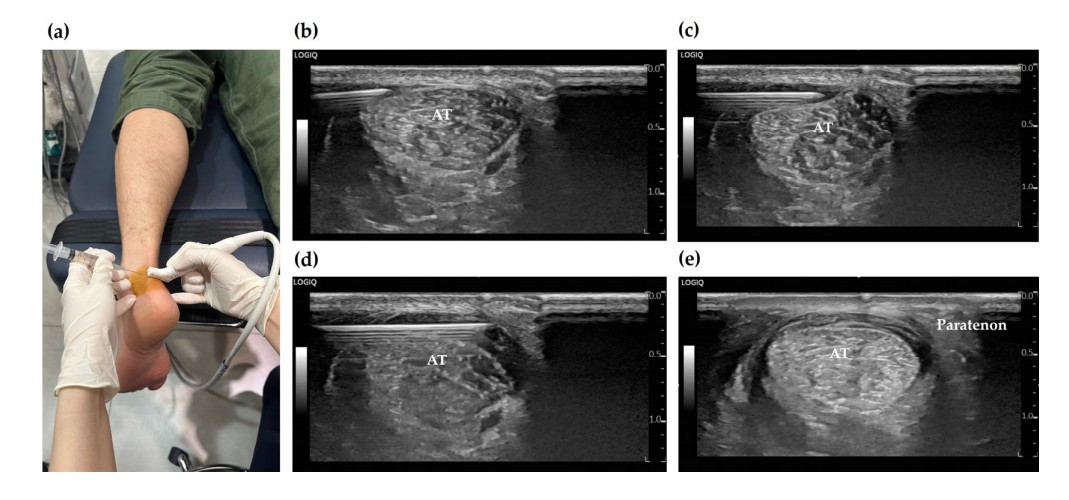

[한의신문] 수술을 권유받을 정도로 심각한 만성 아킬레스건병증 환자에게 병태생리학적 기전에 기반한 초음파를 활용한 약침 치료를 시행한 결과, 통증 감소와 기능 회복에 탁월한 효과를 보였다는 연구결과가 발표돼 관심을 끌고 있다.

이에 연구팀은 안태석 한의영상학회 교육이사(바로한의원)가 개발한 ‘4단계 치료 프로토콜을 적용했다. 이 치료법은 만성 아킬레스건병증의 복합적인 원인을 단계별로 해결하는 것이 특징으로, 1단계: 건 주위염 2단계: 비복근-가자미근 근막통 3단계: 신생혈관 신경성 염증 4단계: 아킬레스건 골건부착부 병증 치료로 구성돼 있다.

47일간 12회의 치료를 시행한 결과, 환자의 발·발목 기능 점수(FAOS)는 통증, 증상, 일상생활, 스포츠 활동, 삶의 질 등 모든 항목에서 뚜렷한 개선을 보였다. 특히 초음파상에서 만성 통증의 주요 원인인 아킬레스건 내부의 신생혈관(neovascularization) 신호가 치료 후 현저히 감소한 것이 확인됐으며, 치료 종료 2개월 후 추적 관찰에서도 재발 없이 호전 상태가 유지됐다.

이와 함께 공동연구자로 참여한 문지현 한의영상학회 교육위원은 이번 연구에 사용된 PDRN 연아약침과 태반 자하거 약침 등은 조직 재생과 항염증 효과가 입증된 안전한 제제라며 특히 초음파를 활용한 시술을 통해 약물을 병변 부위에 정확히 주입하고, 신경 손상 등의 부작용을 최소화할 수 있었다고 말했다.

특히 오명진 한의영상학회 교육위원장(부산대 한의학전문대학원 겸임교수)초음파 진단을 통해 환자에게 직접 통증의 원인이 되는 신생혈관과 병변을 보여주며 치료 과정을 설명함으로써 환자의 신뢰도와 치료 순응도를 높일 수 있었다면서 이번 연구는 진단부터 치료까지 초음파를 활용한 정밀 한의 치료의 우수성을 다시 한번 입증한 사례라고 강조했다.